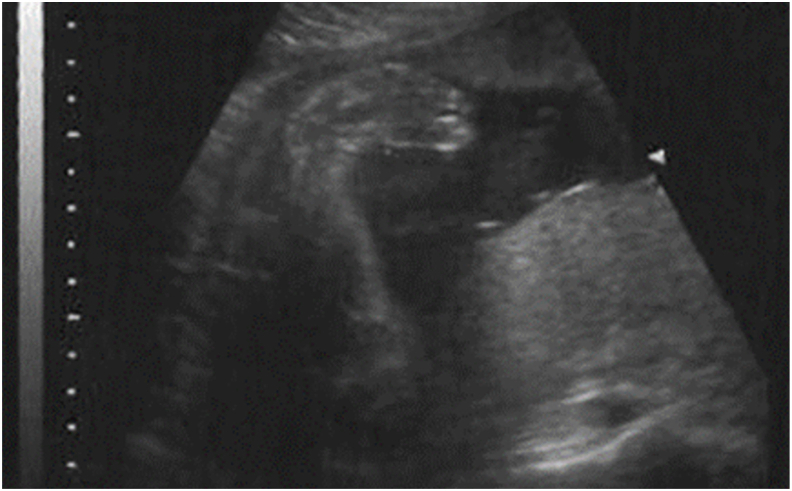

先天性内翻足是一种常见的畸形,影响1 / 1000的新生儿,在常规产前护理中经常被发现。各种各样的检测方法和测试被用来识别胎儿的畸形足和其他先天性异常,包括全超声检查、羊膜穿刺术、绒毛膜绒毛取样或无细胞DNA。较新的研究将特定的基因组序列与内翻足联系起来。对于骨科医生来说,了解各种测试的含义以提供适当的产前咨询是很重要的。早期产前检测马蹄内翻足可以帮助父母为照顾马蹄内翻足的孩子做好准备,并在家庭和临床医生之间建立信任,最终为他们的孩子提供更好的、以患者为中心的护理。关键概念:(1)及时识别和治疗先天性内翻足是促进最佳治疗的必要条件(2)产前诊断通常包括妊娠13-16周时对双脚足底表面的超声检查(3)对于有神经功能障碍或综合征特征的患者,可能需要额外的产后检查(4)遗传标记如PITX1, RBM10, HOX,和CASP(以及其他)已被确定与畸形足的发展有关,并对产前检查和咨询有影响。

Key concepts: (1)Prompt recognition and treatment of congenital clubfoot is imperative to facilitate optimal treatment.(2)Prenatal diagnosis usually consists of sonography of the plantar surface of both feet at 13-16 weeks' gestation.(3)Additional post-natal testing may be indicated in patients with neurological impairment or syndromic features.(4)Genetic markers such as PITX1, RBM10, HOX, and CASP (among others) have been identified as involved in clubfoot development and have implications on prenatal testing and counseling.